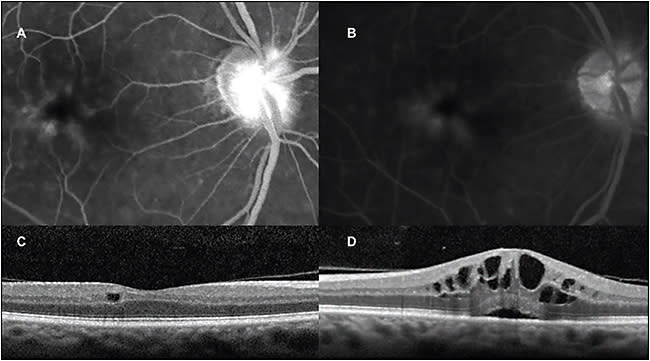

Interestingly, a proportion of patients with active CME demonstrated isolated INL cystic changes in their phakic, asymptomatic fellow eyes (Figure 1). This finding resolved upon treatment of the involved eye with periocular glucocorticoids, supporting the notion that a soluble inflammatory mediator or ocular reflex may be involved in CME.

Figure 1. Isolated inner nuclear layer cystic changes in the phakic fellow eye of a patient with acute pseudophakic cystoid macular edema. A) Arteriovenous phase fluorescein angiogram demonstrating mid-capillary perifoveal leakage six weeks after uncomplicated cataract extraction in the contralateral eye. B) Recirculation phase demonstrating late and mild disc leakage. C) SD-OCT of the the phakic unoperated eye displays isolated inner nuclear layer cysts. D) The operative eye demonstrates typical cystoid macular edema.